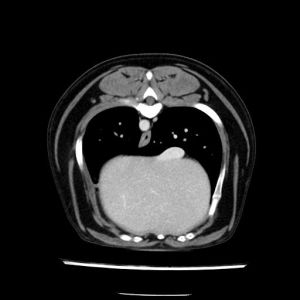

La lesione focale epatica , la ceus,la Tac e il chirurgo .